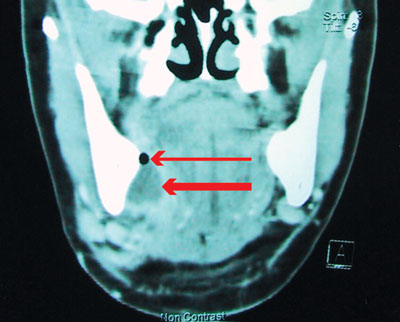

On examination, the patient had difficulty breathing through the mouth. Marked left submandibular swelling, severe trismus and halitosis were noted. He was afebrile, but had a white cell count of 16.3 x 109/L (normal range, 4.0–11.0 x 109/L), neutrophilia of 13.1 x 106/L (normal range, 2.0–7.5 x 109/L) and a serum C-reactive protein level of 207 mg/L (normal range, < 10 mg/L). An OPG revealed a deep dental filling of the lower left second molar and a carious lower left wisdom tooth.

He was admitted for airway observation and given intravenous benzylpenicillin and metronidazole. The next day he was unable to completely open his mouth. After awake fibreoptic intubation, the two teeth were removed and the abscess drained. (The clinical and radiological findings for a patient with a similar diagnosis are shown in Box 1, B–D.)